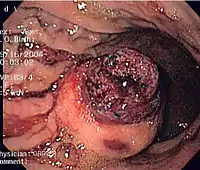

Endoscopic image of GIST in fundus of stomach, seen on retroflexion.

Same GIST seen on forward view of the endoscope showing overlying clot.

CT scanning is often undertaken (see the radiology section).

The definitive diagnosis is made with a biopsy, which can be obtained endoscopically, percutaneously with CT or ultrasound guidance or at the time of surgery. A biopsy sample will be investigated under the microscope by a pathologist physician. The pathologist examines the histopathology to identify the characteristics of GISTs (spindle cells in 70-80%, epitheloid aspect in 20-30%). Smaller tumors can usually be confined to the muscularis propria layer of the intestinal wall. Large ones grow, mainly outward, from the bowel wall until the point where they outstrip their blood supply and necrose (die) on the inside, forming a cavity that may eventually come to communicate with the bowel lumen.